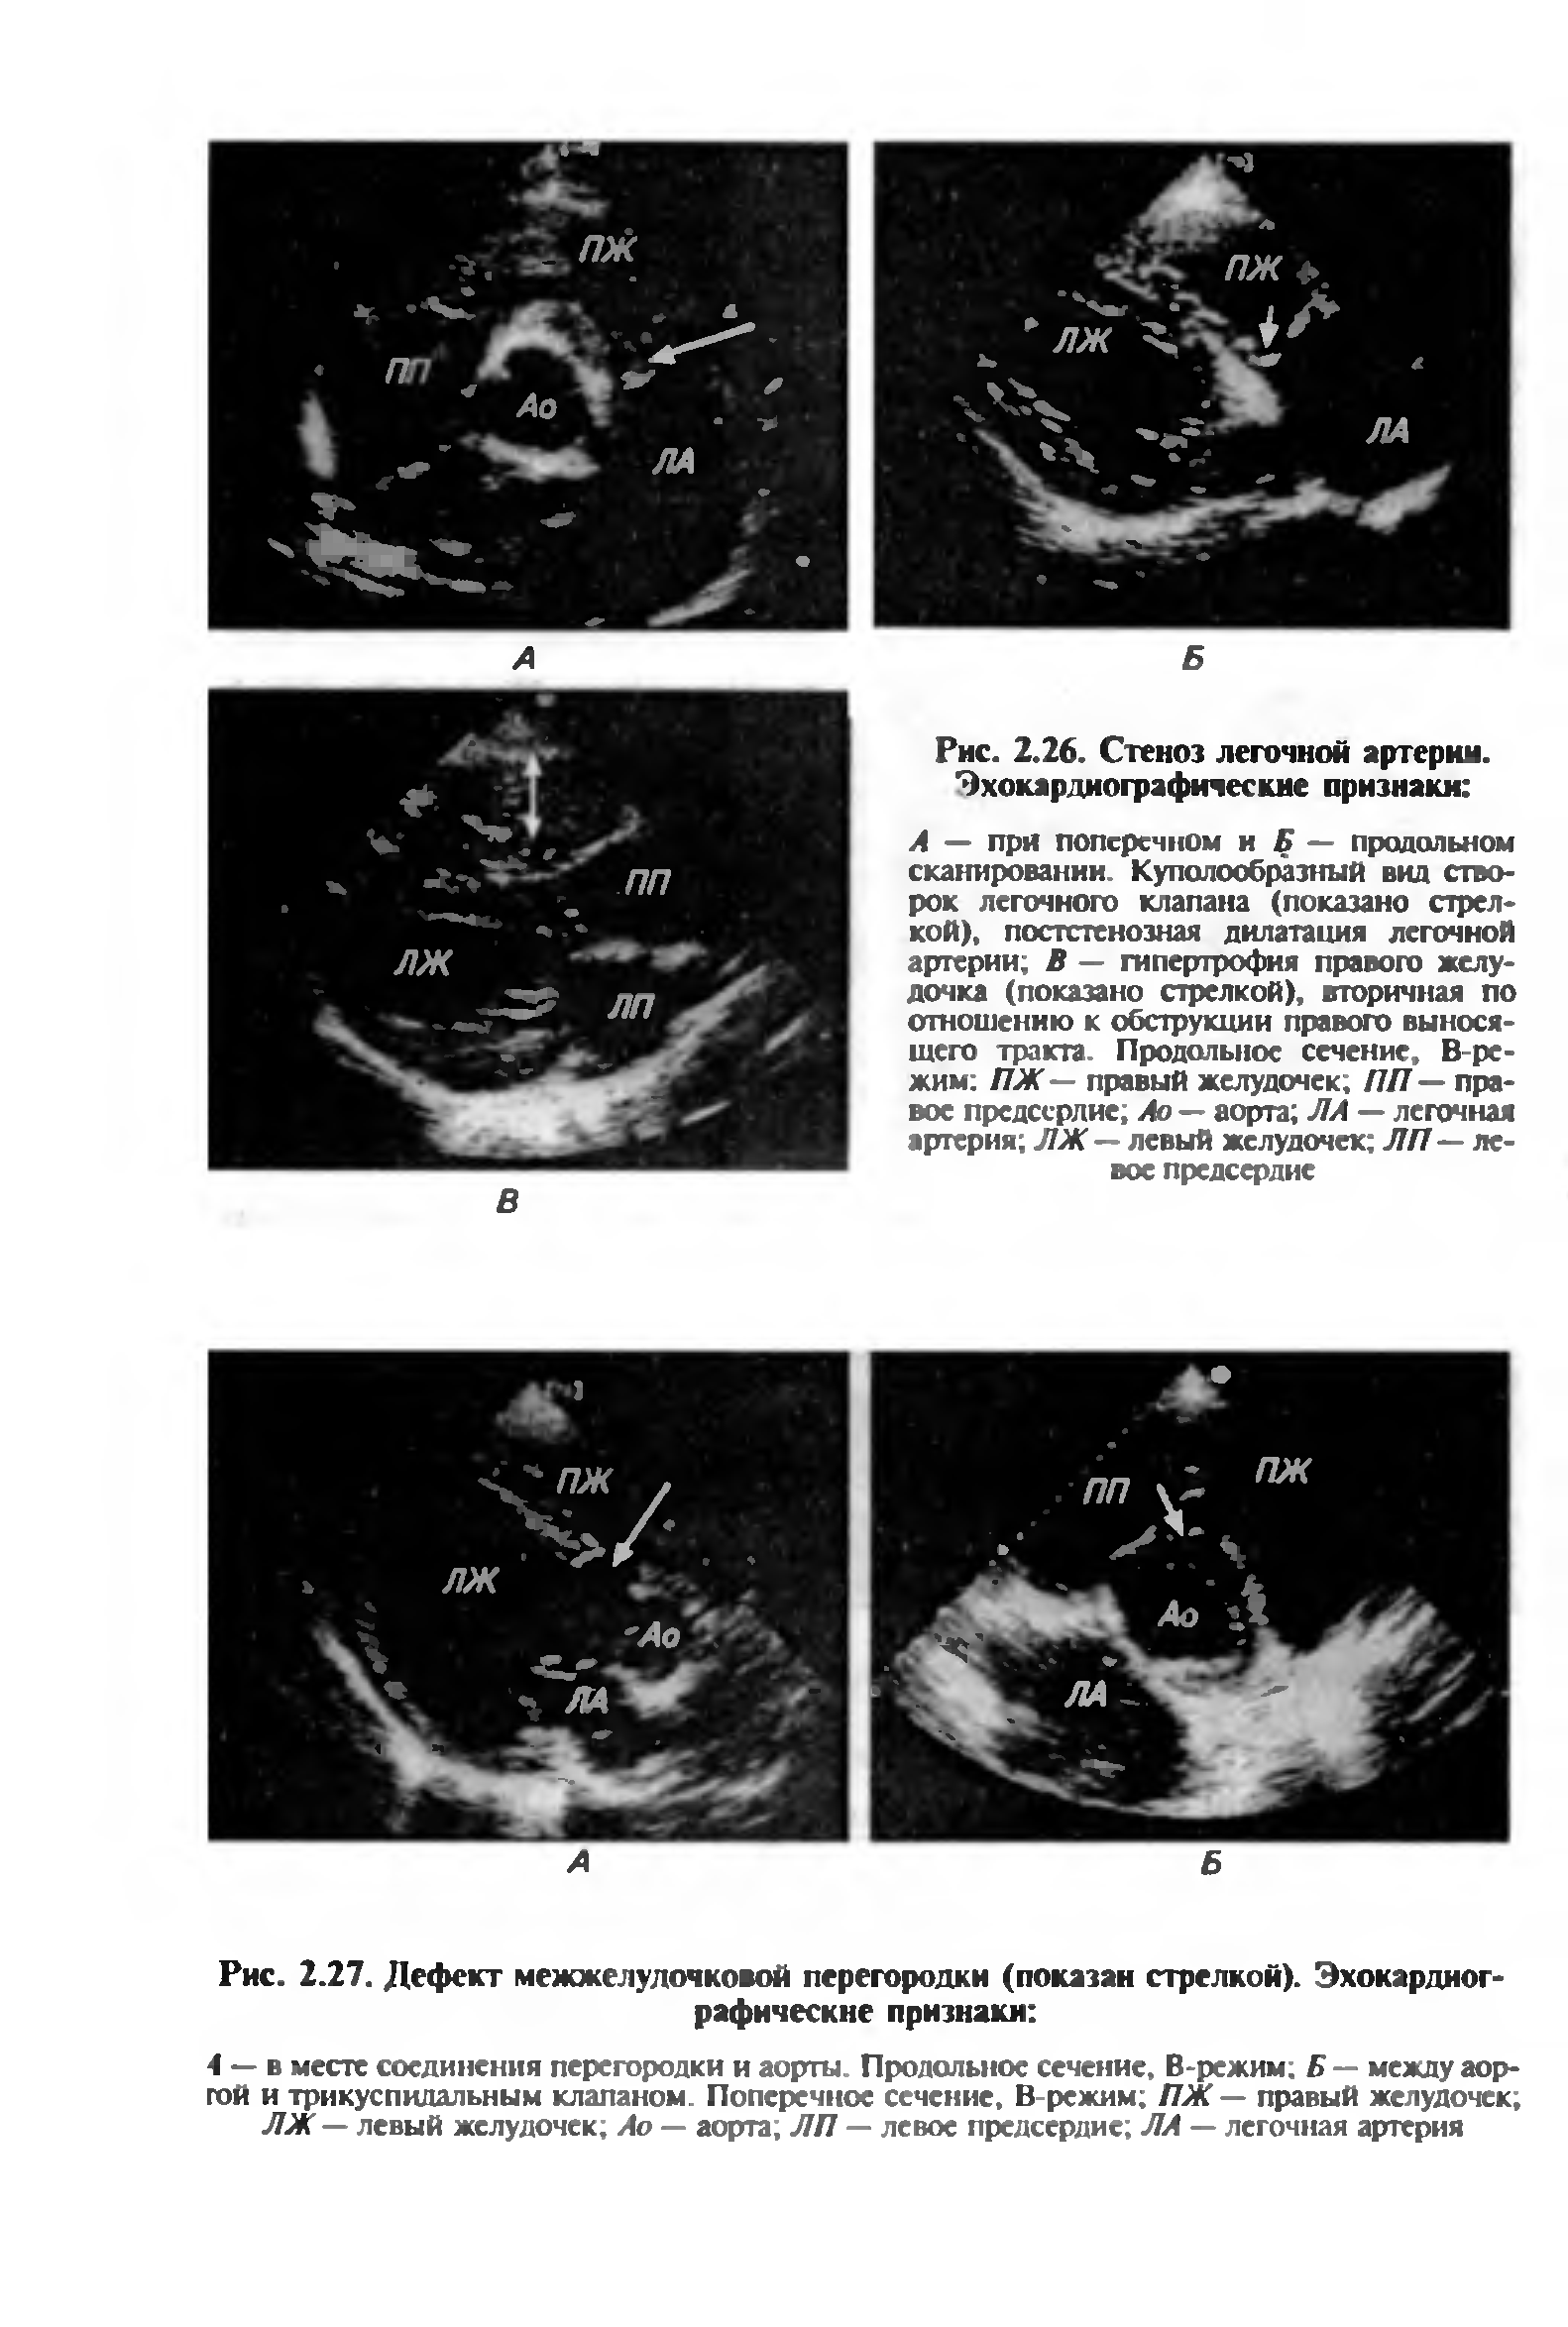

"Ультразвуковая диагностика внутренних болезней мелких домашних животных" - читать интересную книгу автора (Шабанов А.М., Зорина А.И., Ткачёв-Кузьмин А.А.,...)